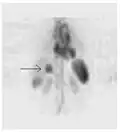

-

Normal whole body PET/CT scan with FDG-18. The whole body PET/CT scan is commonly used in the detection, staging and follow-up of various cancers. -

Abnormal whole body PET/CT scan with multiple metastases from a cancer. The whole body PET/CT scan has become an important tool in the evaluation of cancer.